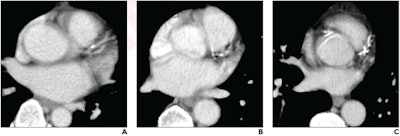

Atherosclerotic cardiovascular disease is the leading cause of death in the U.S., and coronary artery calcium (CAC) is a strong determining factor for predicting adverse event risk, the group explained. Incidental CAC can be found on nongated chest CT that patients undergo for other indications, and radiologists' visual assessment of CAC on these nongated exams has been shown to correspond to Agatston scores.

To this end, Fresno and colleagues conducted a study that included 260 patients who underwent nongated chest CT for indications besides CAC assessment (of these, 116 had contrast-enhanced exams and 144 had exams without contrast) and a cardiac calcium score CT within a 12-month period. A cardiothoracic radiologist scored CAC on chest CT using a visual ordinal assessment that consisted of the following: absent (0), mild (1 to 99), moderate (100 to 299), or severe (> 300).

CAC was also evaluated with software that calculated volume across all identified plaque and produced a total Agatston score. To determine reader agreement between the visual assessment and cardiac CT results, a second radiologist evaluated a subset of 50 chest CT exams.